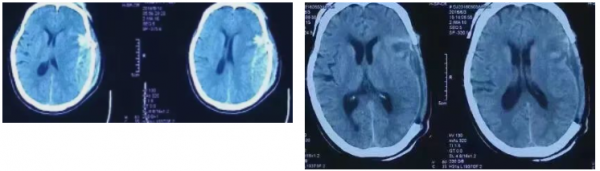

一天,張教授值班,一位女士被突如其來的車輛重撞,120送達(dá)時,人已深度昏迷,CT下見硬膜下、硬膜外血腫,腦疝形成。

患者生命垂危,且無家屬陪同,緊急時刻,“救人要緊”!張教授果斷決定手術(shù)治療,報請?jiān)嚎傊蛋嗪螅?/span>帶領(lǐng)值班醫(yī)生展開搶救工作。

經(jīng)過數(shù)小時的努力,搶救手術(shù)圓滿成功,病人清醒且無后遺癥。事后家屬表示:“醫(yī)患關(guān)系緊張的今天仍冒險救人,醫(yī)德高尚!”并送錦旗以示感謝!